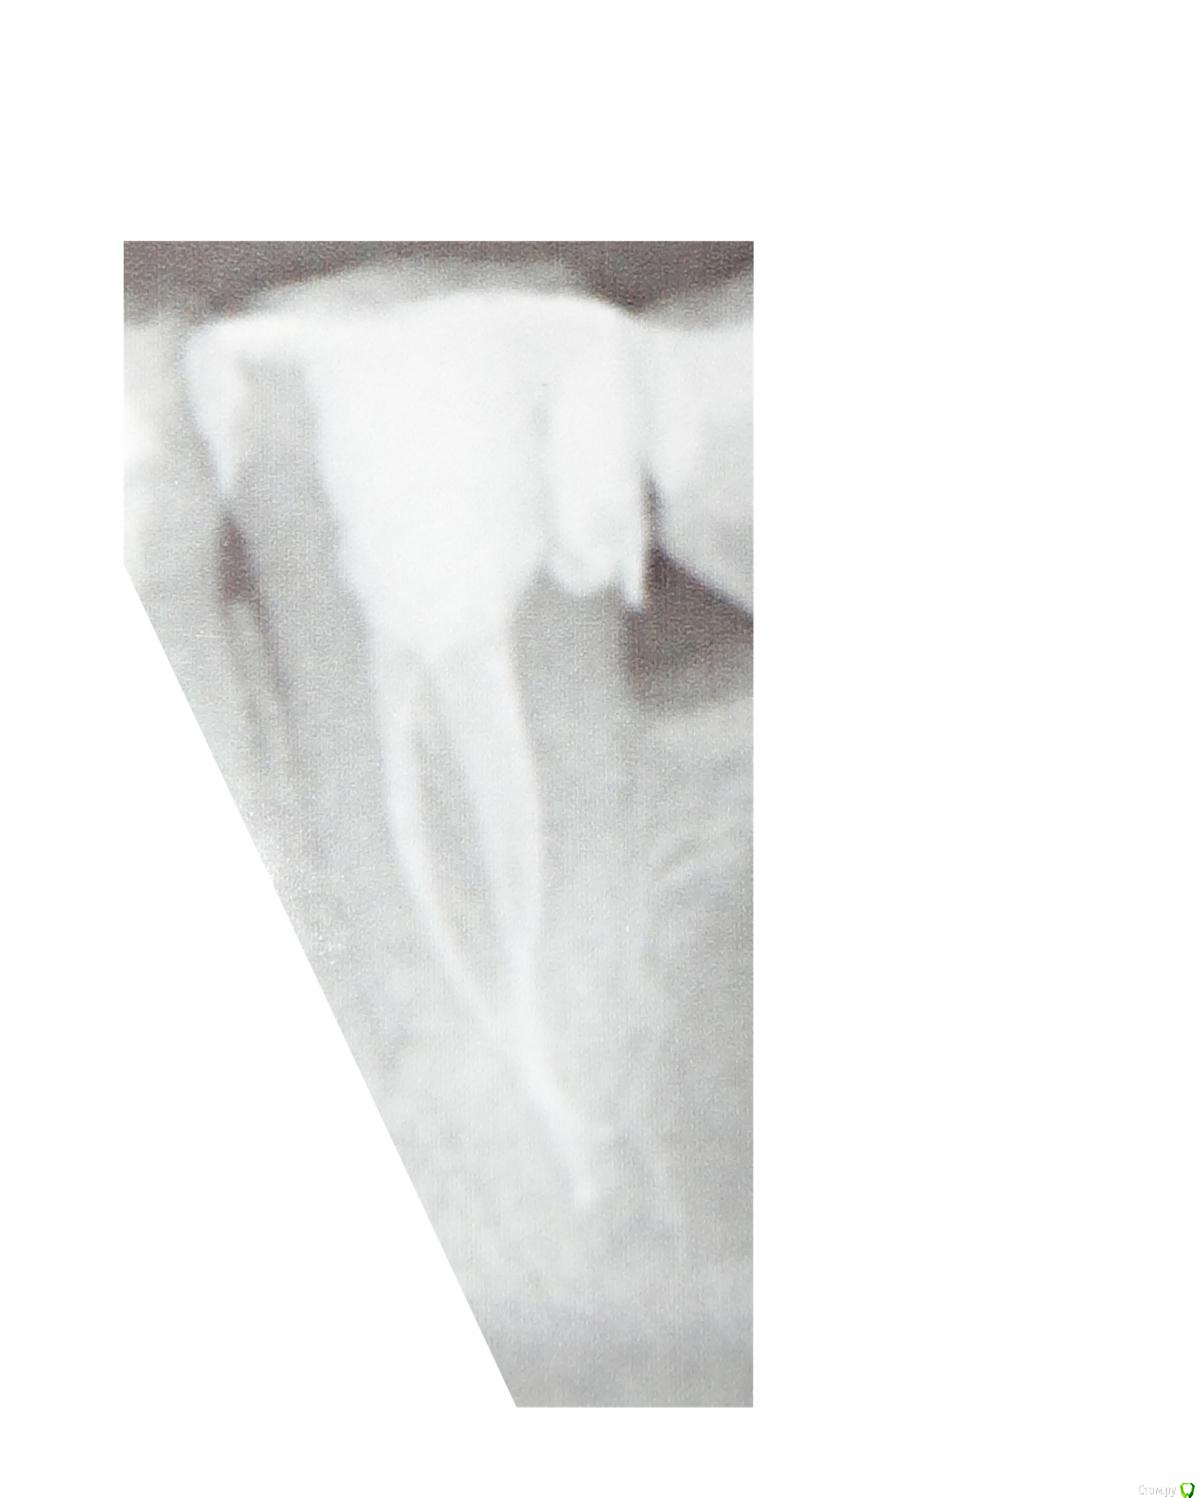

Mikalaika Опубликовано 8 июня, 2020 Автор Поделиться Опубликовано 8 июня, 2020 Это 2D снимок (фотографии сделаны с распечтки на фотобумаге) Ссылка на комментарий

St. Опубликовано 10 июня, 2020 Поделиться Опубликовано 10 июня, 2020 По 2д, насколько позволяет рассмотреть качество, все выглядит хорошо Ссылка на комментарий